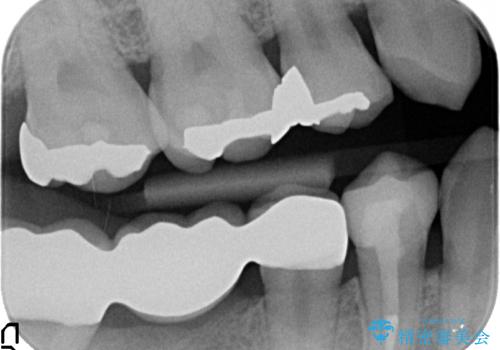

右下7については、遠心の歯の高さがなく、また、同様に歯肉縁下にカリエスがあったため、手術を行い改善しました。

手術はディスタルウェッジとAPFを併せて行なっています。

右下6については、物理的には歯を使うことは可能ですが、残すと悪くなっていくのを避けられないような修復しかできないため、長期的な展望が立たないため抜歯をお勧めしました。

短期的にまた抜歯になるような修復のやりかえは、お勧めしておりません。